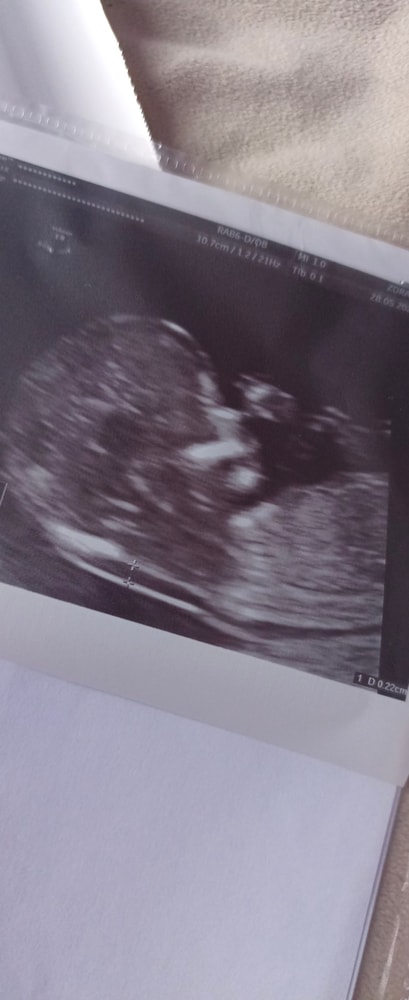

12 нед и 6 дней

Была на скрининговое узи, сразу же после сдала кровь.

ЧСС 162 уд/мин

КТР 71 мм (13 нед 2 дня)

БПР 74 мм (14 нед 1 д)

ОГ 95 мм (14 нед 1 д)

ТВП 2,2 мм

НК визуализируется

Сердце, конечности, позвоночник, внутренние органы, глазницы, профиль

Шейка матки 36 мм

Посмотрели даже пол, пока врач смотрела через брюшную стенку, то давала 85-90% вероятность, что мальчик, а потом стала через влагалище смотреть и сомнений, говорит, не осталось

Фото: